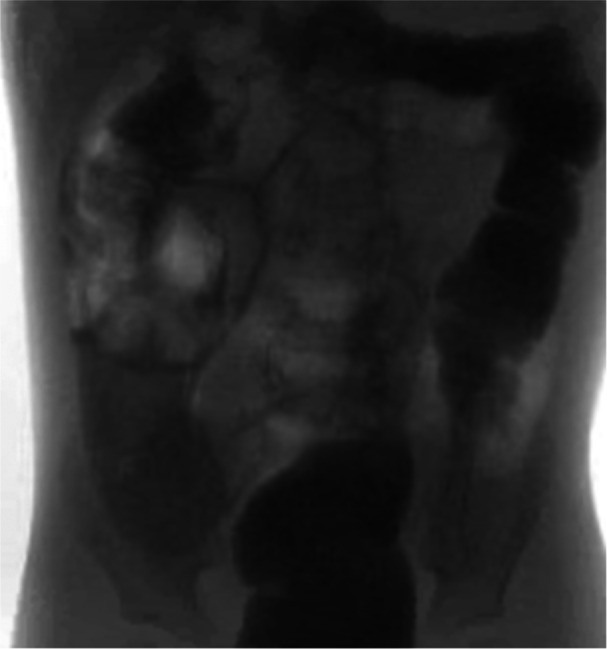

Pediatric intestinal pseudo-obstruction (PIPO) is a rare and severe disorder of gastrointestinal (GI) motility; patients with PIPO display signs and symptoms of intestinal obstruction in the absence of occluding lesions. Chronic atrial and intestinal dysrhythmia (CAID) syndrome is an exceedingly rare autosomal recessive disorder caused by mutations in the SGO1 gene; SGO1 mutations disrupt the cohesin complex, a protein involved in chromosome organization during cell division and hence, DNA stability. CAID leads to both GI and cardiac dysfunction. This case report highlights an exceptional instance of early-onset pediatric CAID marked by recurrent pseudo-obstruction and, notably, developmental delay, which has not been previously described. The case emphasizes the importance of genetic evaluation in pediatric patients with unexplained pseudo-obstruction, and the importance of multidisciplinary management.

Abstract Image